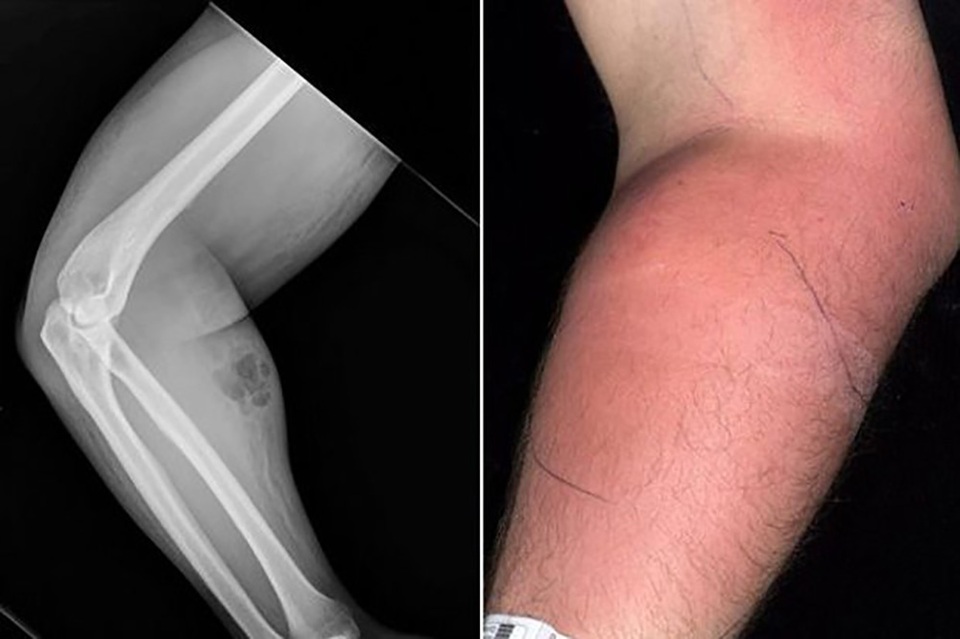

Các bác sĩ đã phát hiện ra người đàn ông có biểu hiện kì lạ sau khi anh ta đến bệnh viện với một cánh tay bị sưng, áp xe cùng với tình trạng đau lưng mãn tính của anh ta.

Cánh tay của người đàn ông sưng lên với tinh dịch bị rò rỉ vào các mô xung quanh do tiêm không thành công. Liều cuối cùng của anh ta là gấp ba lần bình thường trước đó anh ta vẫn tiêm.

Người đàn ông này đã nói với các bác sĩ về tinh dịch của mình có thể chữa bệnh và đã thừa nhận phương pháp điều trị cải tiến của anh ấy mà anh ấy đã thực hiện trong một năm rưỡi. Anh ta đã tự tiêm cả tĩnh mạch và tiêm bắp bằng kim tiêm dưới da.